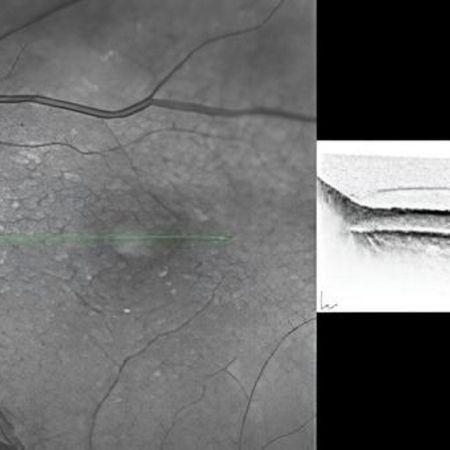

Optische Kohärenztomographie (OCT)

• Die tomographische Untersuchung, kurz OCT (Optische Kohärenztomographie) erstellt Querschnittsbilder der Netzhaut, des Sehnervs und der Hornhaut und ist eine wichtige Zusatzuntersuchung neben dem Spaltlampenmikroskop.

• Die Untersuchung ist nicht invasiv, ungefährlich, berührungslos und schmerzfrei.

• Mein Gerät nutzt die weltweit modernste Technologie und ermöglicht genaueste Diagnose über Erkrankungen der oben genannten Organe. Insbesondere für die Erkennung und Kontrolle der häufigen AMD (Altersabhängige Makula Degeneration), der Diabetischen Netzhauterkrankung und des Glaukoms (Grüner Star) ist die Optische Kohärenztomographie (OCT) von unschätzbarem Wert.

• Die OCT gehört heute zur Standarduntersuchung vieler Augenerkrankungen, die dann innerhalb kürzester Zeit diagnostiziert und dokumentiert werden können.